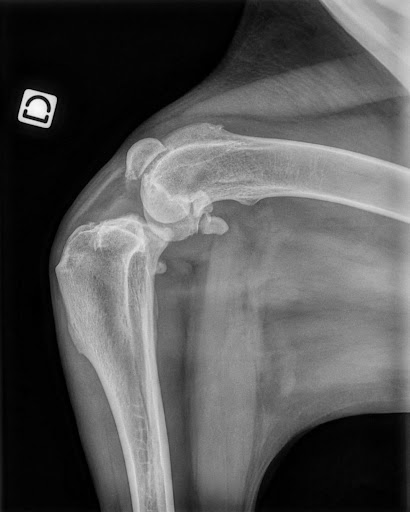

방사선 검사 (X-ray)

관절 간격의 변화나 경골의 위치 이동 등을 통해 손상 가능성을 추정할 수 있습니다.